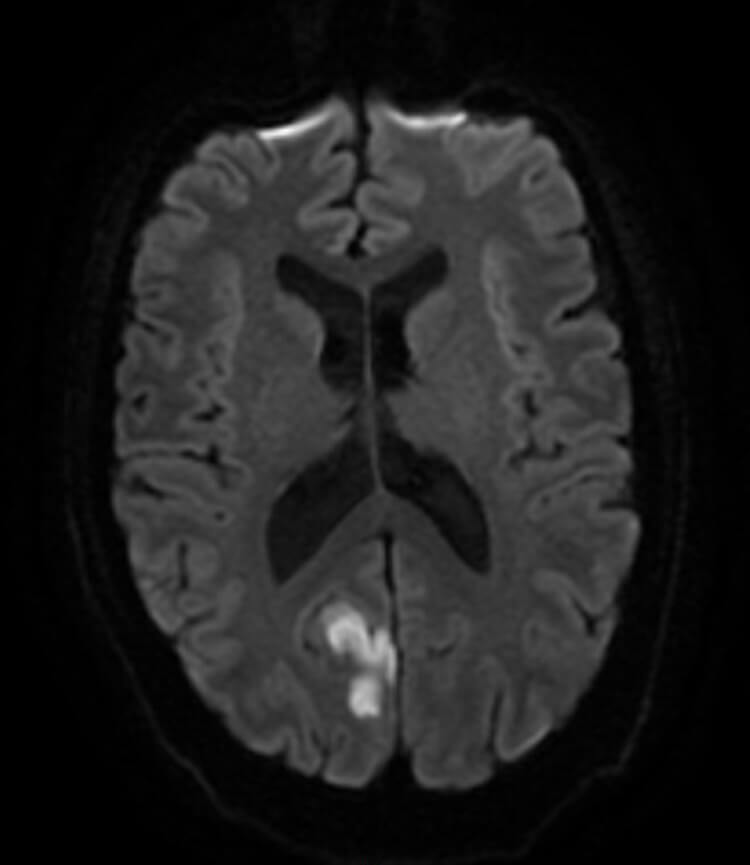

Figure 1: MRI head showing right occipital lesion infarct that produced the left inferior homonymous quadrantopia.

A stroke team assessment gave the patient a NIHSS score of 1. A CT head and a MRI head was ordered. The CT head showed an extremely subtle decreased density in the right occipital lobe which was suggestive of a sub-acute infarct. MRI DWI imaging confirmed the lesion. Based on the above workup, the diagnosis was confirmed as sub-acute right occipital infarct which was the cause of the left homonymous inferior quadrantanopia field defect.

Although it is classically taught in medical school that quadrantopias localise to the parietal lobe (inferior quadrantopia) or temporal lobe (superior quadrantopia), specific field defects do not always point a specific lesion location. A recent study actually showed that 76% of lesions that cause inferior quadrantopias were found in the occipital lobe, whilst only 22% were isolated to the parietal lobe [1]. Lesions must be confirmed with neuroimaging, and in the case presented above, MRI DWI imaging showed a right occipital infarct as the cause of the left inferior quadrantopia (Figure 1).